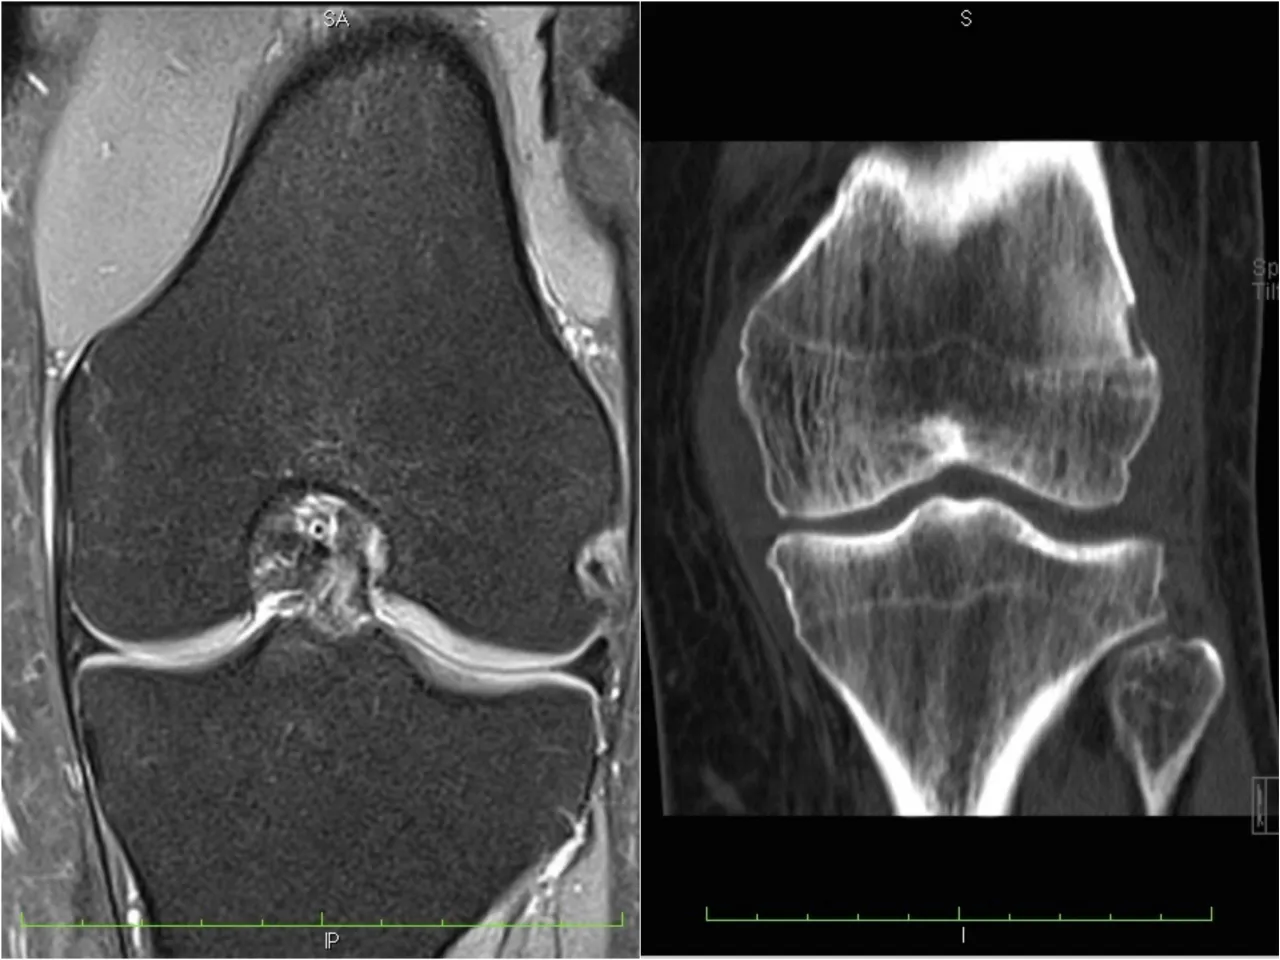

USG, RTG czy Rezonans Magnetyczny (MRI)? Wyjaśniamy, co pokaże każde z badań

Po badaniu fizykalnym, lekarz może zlecić badania obrazowe, aby potwierdzić diagnozę i ocenić zakres uszkodzeń:

- RTG (rentgen): Jest to badanie, które przede wszystkim służy do wykluczenia złamań kości. Skręcenie kolana to uraz tkanek miękkich, więc RTG nie pokaże uszkodzeń więzadeł czy łąkotek, ale jest ważne, aby upewnić się, że nie ma towarzyszących złamań.

- USG (ultrasonografia): Pozwala na dynamiczną ocenę tkanek miękkich, takich jak więzadła poboczne, ścięgna czy mięśnie. Jest przydatne do szybkiej oceny obecności płynu w stawie i niektórych uszkodzeń więzadeł, zwłaszcza MCL.

- Rezonans Magnetyczny (MRI): To "złoty standard" w diagnostyce urazów kolana. MRI zapewnia bardzo szczegółowy obraz wszystkich struktur stawu więzadeł (krzyżowych, pobocznych), łąkotek, chrząstki stawowej, kości i innych tkanek miękkich. Pozwala precyzyjnie ocenić rodzaj i stopień uszkodzenia, co jest kluczowe dla zaplanowania dalszego leczenia.